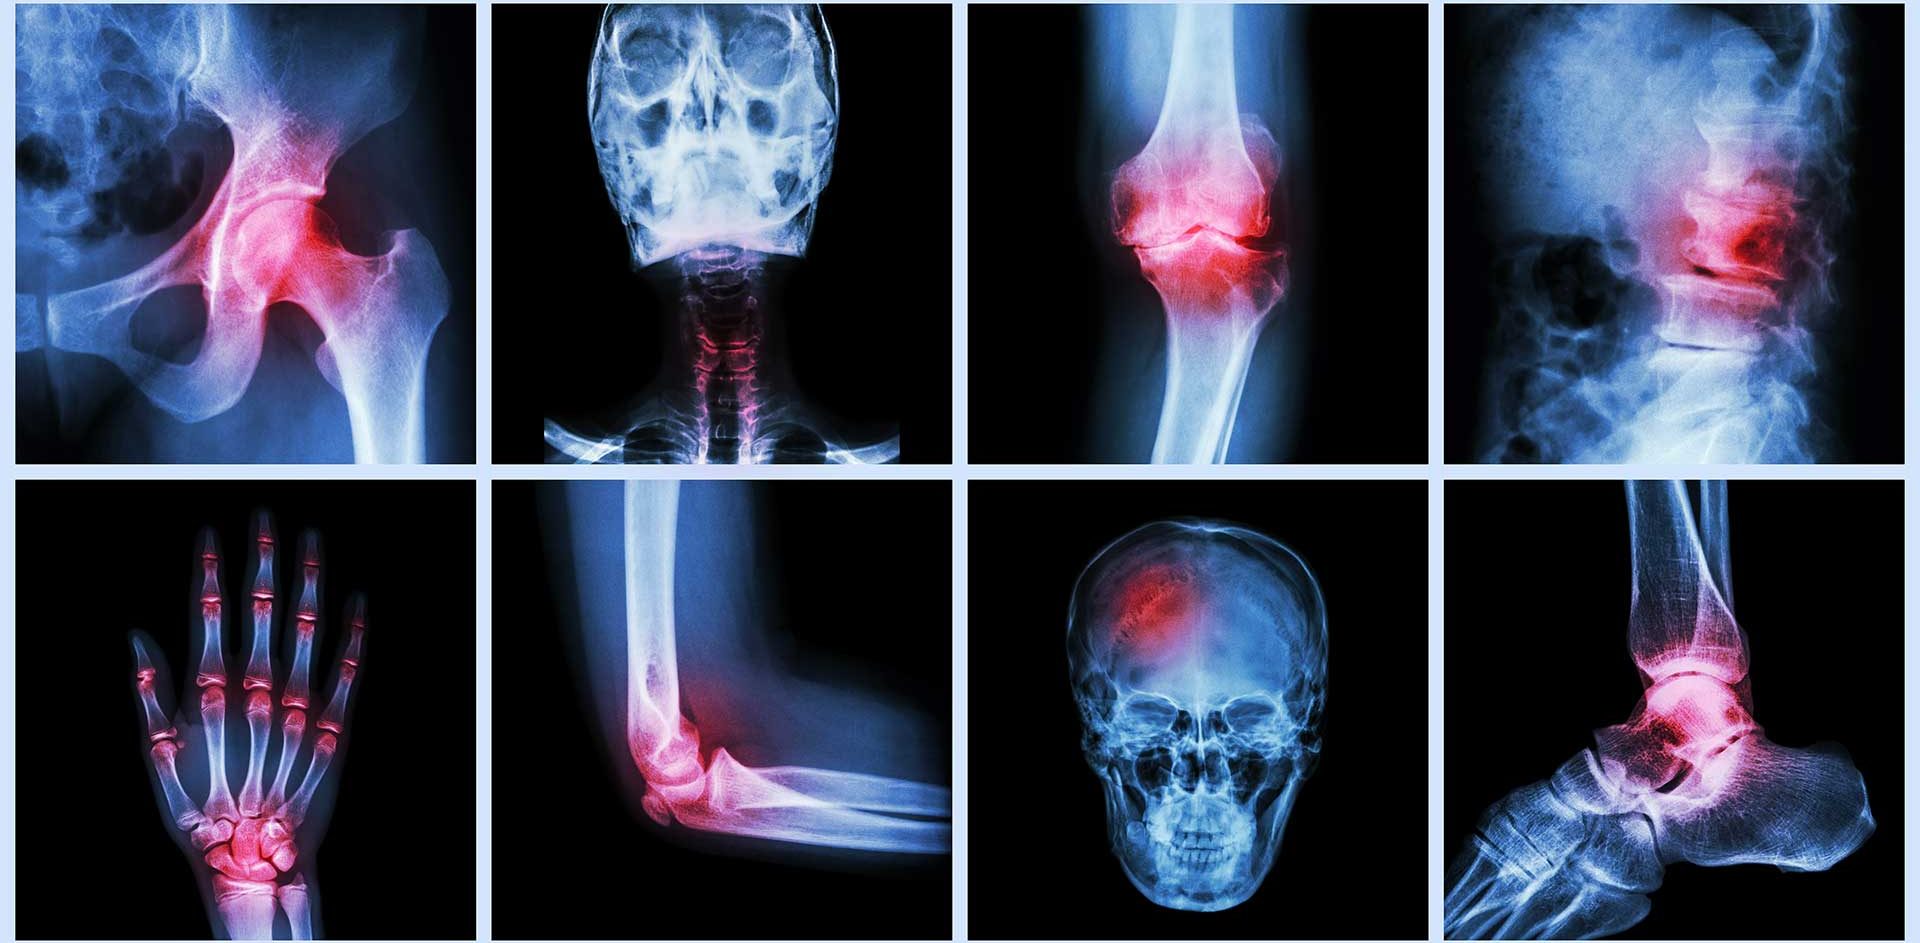

L’algodystrophie, également appelée syndrome douloureux régional complexe (SDRC), est une affection chronique caractérisée par une douleur intense, souvent brûlante, accompagnée d’œdème, de raideur articulaire, de modifications cutanées (température, couleur) et d’une sensibilité accrue dans une région du corps, généralement un membre. Elle survient souvent après un traumatisme (fracture, chirurgie) ou une immobilisation prolongée, mais peut aussi apparaître sans cause évidente[^1].

Le mécanisme de l’algodystrophie implique une dysfonction du système nerveux central et périphérique, avec une inflammation neurogène, une altération de la microcirculation et une hypersensibilité des nocicepteurs. Cette condition affecte à la fois le corps et l’esprit, car la douleur chronique entraîne souvent stress, anxiété et dépression, créant un cercle vicieux[^2]. Dans ce contexte, l’acupuncture, pratique issue de la médecine traditionnelle chinoise (MTC), émerge comme une thérapie complémentaire pour soulager la douleur, réduire l’inflammation et restaurer l’équilibre émotionnel, unifiant ainsi corps et esprit. Cette première partie explore les aspects fondamentaux de l’algodystrophie, tandis que la deuxième partie se concentrera sur l’apport de l’acupuncture.